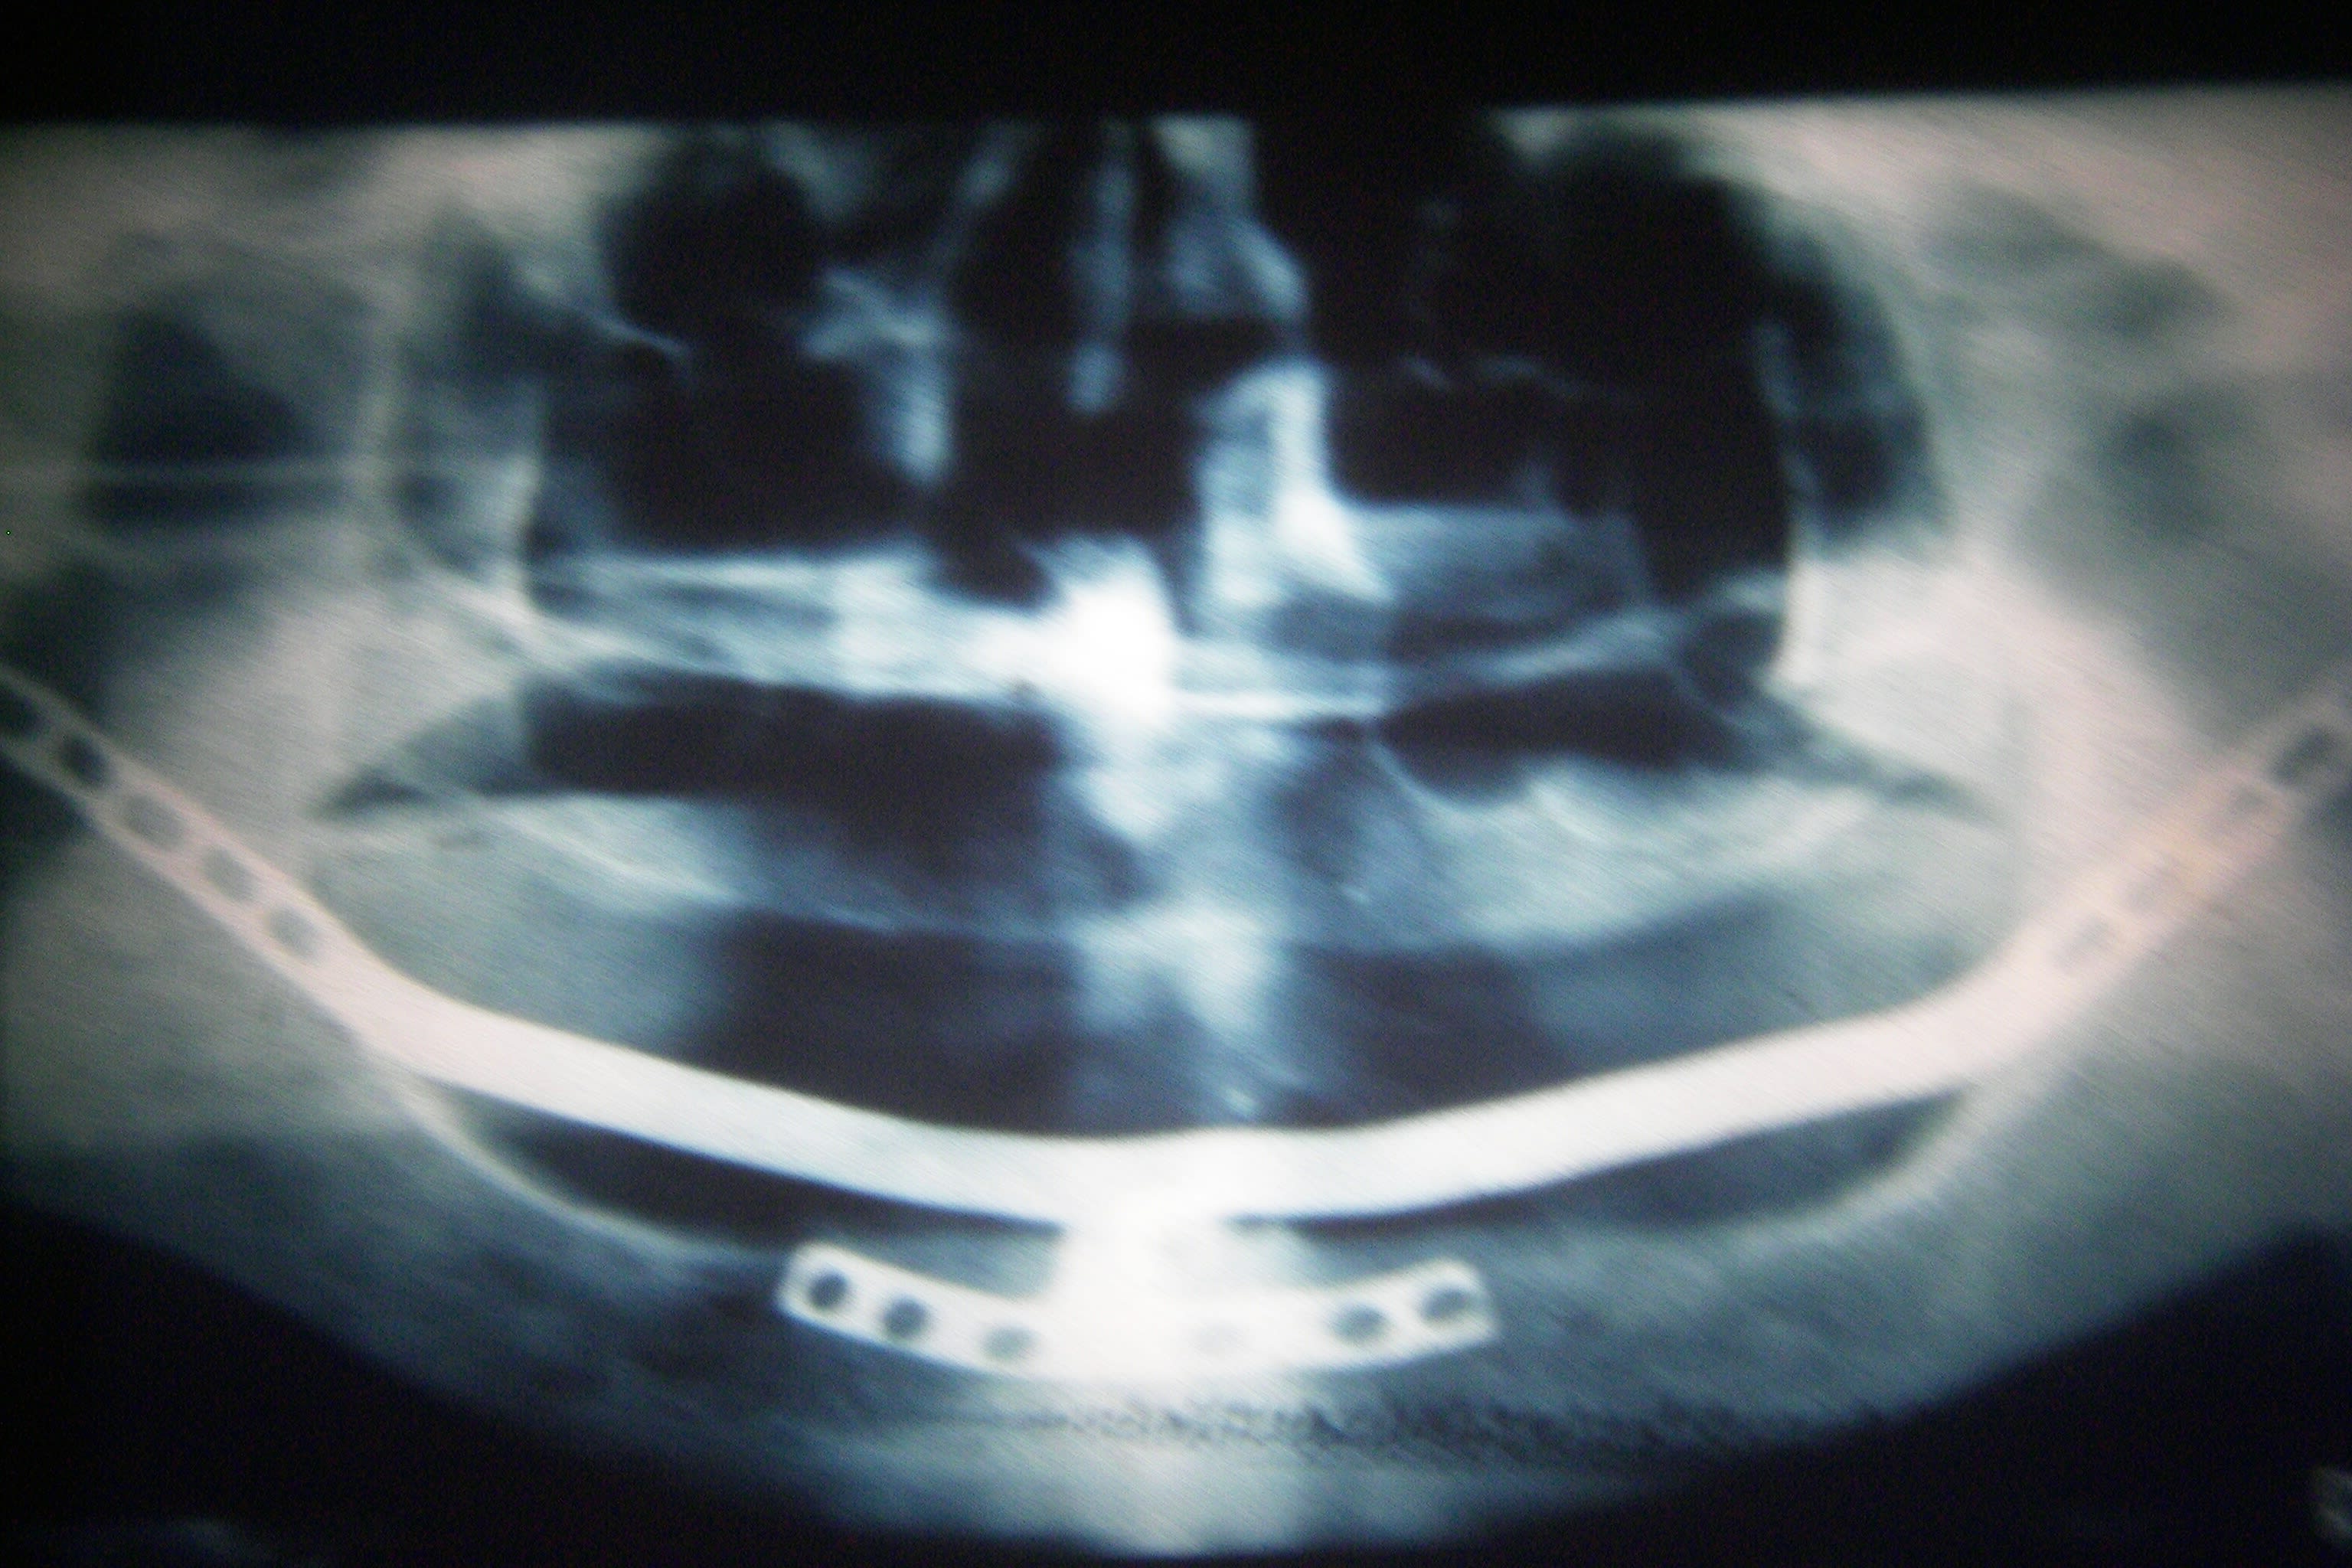

saurais tu par hasard qui est l'auteur de ce comblement de sinus armé au titane ?

encore qu'un disk et un structure ... on se doute )

Sans doute un pionnier 😊. Au dĂ©but je pense qu'ils ont un peu prĂšs tout essayĂ©. La plus marrante a Ă©tĂ© publiĂ©e dans la revue Titane (celle dont tu parles)